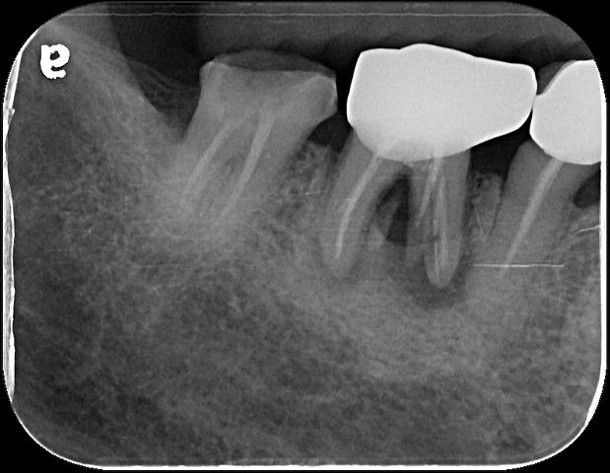

治療後根尖片